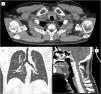

Los tumores glómicos de tráquea son lesiones de presentación inusual o rara, representan el 2% de los tumores de tejidos blandos, son benignos, y se generan en el tejido mesenquimal de las anastomosis arteriovenosas1. La presentación clínica es inespecífica y con frecuencia se diagnostican erróneamente con enfermedades respiratorias como asma bronquial, bronquitis, entre otras. Las manifestaciones clínicas severas se dan cuando se obstruye>70% de la luz traqueal y se dan con la presencia de disnea de mínimos esfuerzos2. Su diagnóstico puede ser incidental en estudio de imágenes, o con la presentación de síntomas respiratorios de larga evolución u obstrucción severa de la vía respiratoria superior. Continúa el debate respecto a su tratamiento y los resultados a largo plazo, teniendo en cuenta las diversas alternativas a la resección traqueal segmentaria, incluido el tratamiento endoscópico o la radioterapia. El tratamiento quirúrgico tiene como objetivo eliminar la obstrucción de la vía respiratoria, curación definitiva en lesiones de crecimiento lento y prolongar la supervivencia a largo plazo3. Informamos de un caso de tumor glómico de tráquea con obstrucción de la luz traqueal del 90%, que requirió plastia traqueal con la resección tumoral como tratamiento definitivo, describimos el manejo y actualización de la literatura. Hombre de 55 años con antecedentes de cirugías previas de herniorrafia umbilical, hemorroidectomía, septoplastia, covid 19 (enfermedad leve), quien presentó desde hacía 6 meses tos seca, ronquidos, acompañado de disnea de medianos esfuerzos, recibiendo tratamiento médico para asma bronquial sin disminución o remisión de los síntomas. En la tomografía de cuello y tórax se observó tumor de densidad definida ligeramente irregular, protruyendo desde la pared posterior y lateral derecha aproximadamente a 3,5cm subglótica, pediculada de 12 x 15mm de diámetro que se proyecta hacia la luz traqueal que mide 12,5 x 22 x 15mm, densidad ligeramente heterogénea con coeficiente de atenuación entre – 26 y 17 UH que condiciona estenosis de luz traqueal del 90%, sin compromiso esofágico y sin evidencia de adenopatías locorregionales (figs. 1 y 2). En la broncoscopia se evidenció una masa vegetante infiltrativa que se origina en porción posterior de la tráquea por debajo de primer anillo traqueal, vascularizada con membranas blanquecinas adheridas, que condiciona una obstrucción del 90% de la luz traqueal, por su alto riesgo de sangrado y asfixia se decidió tratamiento quirúrgico (fig. 3). Se realiza tratamiento quirúrgico de urgencia que consistió en la resección de masa tumoral de 12 x 20 x 15mm de diámetro de aspecto sólido, multilobulado a nivel de segundo anillo traqueal en la pared posterior traqueal (pars membranacea) y plastia traqueal.

Tomografía de cuello y tórax: a) corte axial, b) corte coronal y c) corte sagital. El tumor protruye de la pared posterior y lateral derecha de la tráquea, pediculada de 12 x 15mm de diámetro que se proyecta hacia la luz traqueal que mide 12,5 x 22 x 15mm, coeficiente de atenuación– 26 y 17 UH, que condiciona estenosis de luz traqueal del 90%, sin compromiso esofágico y sin evidencia de adenopatías locorregionales.